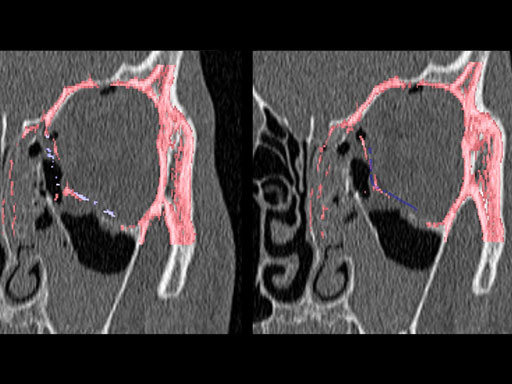

30-year-old male with fracture of left orbital floor and involvement of medial wall.

Case provided by Marc C Metzger, Freiburg, Germany

Fig 1 CT scan with fused image of virtual prebent orbital plate.